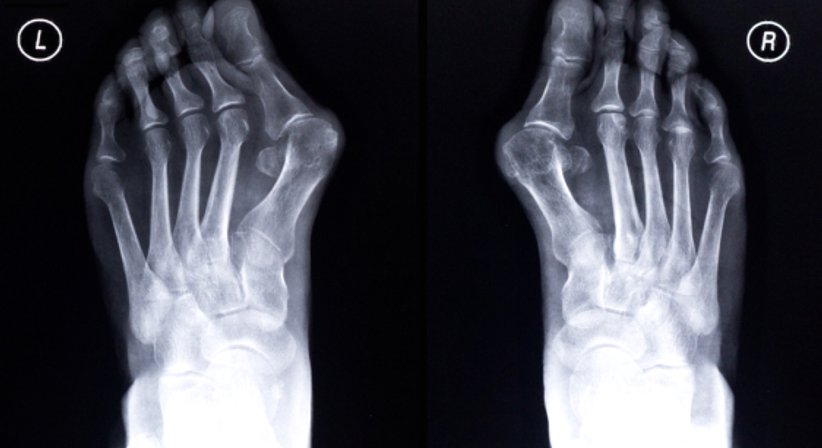

1.Hallux valgus

Ein Hallux valgus, auch Ballenzeh genannt, ist eine Fehlstellung, bei der sich der Mittelfußknochen nach außen bewegt und die Großzehe zu den Mittelzehen. Die Bildung eines Hallux valgus wird durch das tragen hochhackiger und spitz zulaufender Schuhe begünstigt. Als Folge wird das Großzehengrundgelenk stärker abgenutzt. Einlagen und orthopädische Schuhe helfen, die Schmerzen in den Zehen zu verringern. Der Hallux valgus bildet sich jedoch durch diese Behandlung nicht zurück. Das kann nur durch eine Operation erreicht werden, bei der die Stellung der Großzehe korrigiert wird.